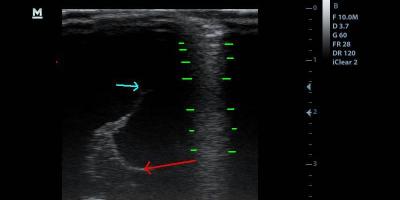

Brain Scan Brain Scan in a Chihuahua Puppy/ Έλεγχος για υδροκέφαλο σε φυλή Τσιουάουα. 22 Απριλίου, 2014